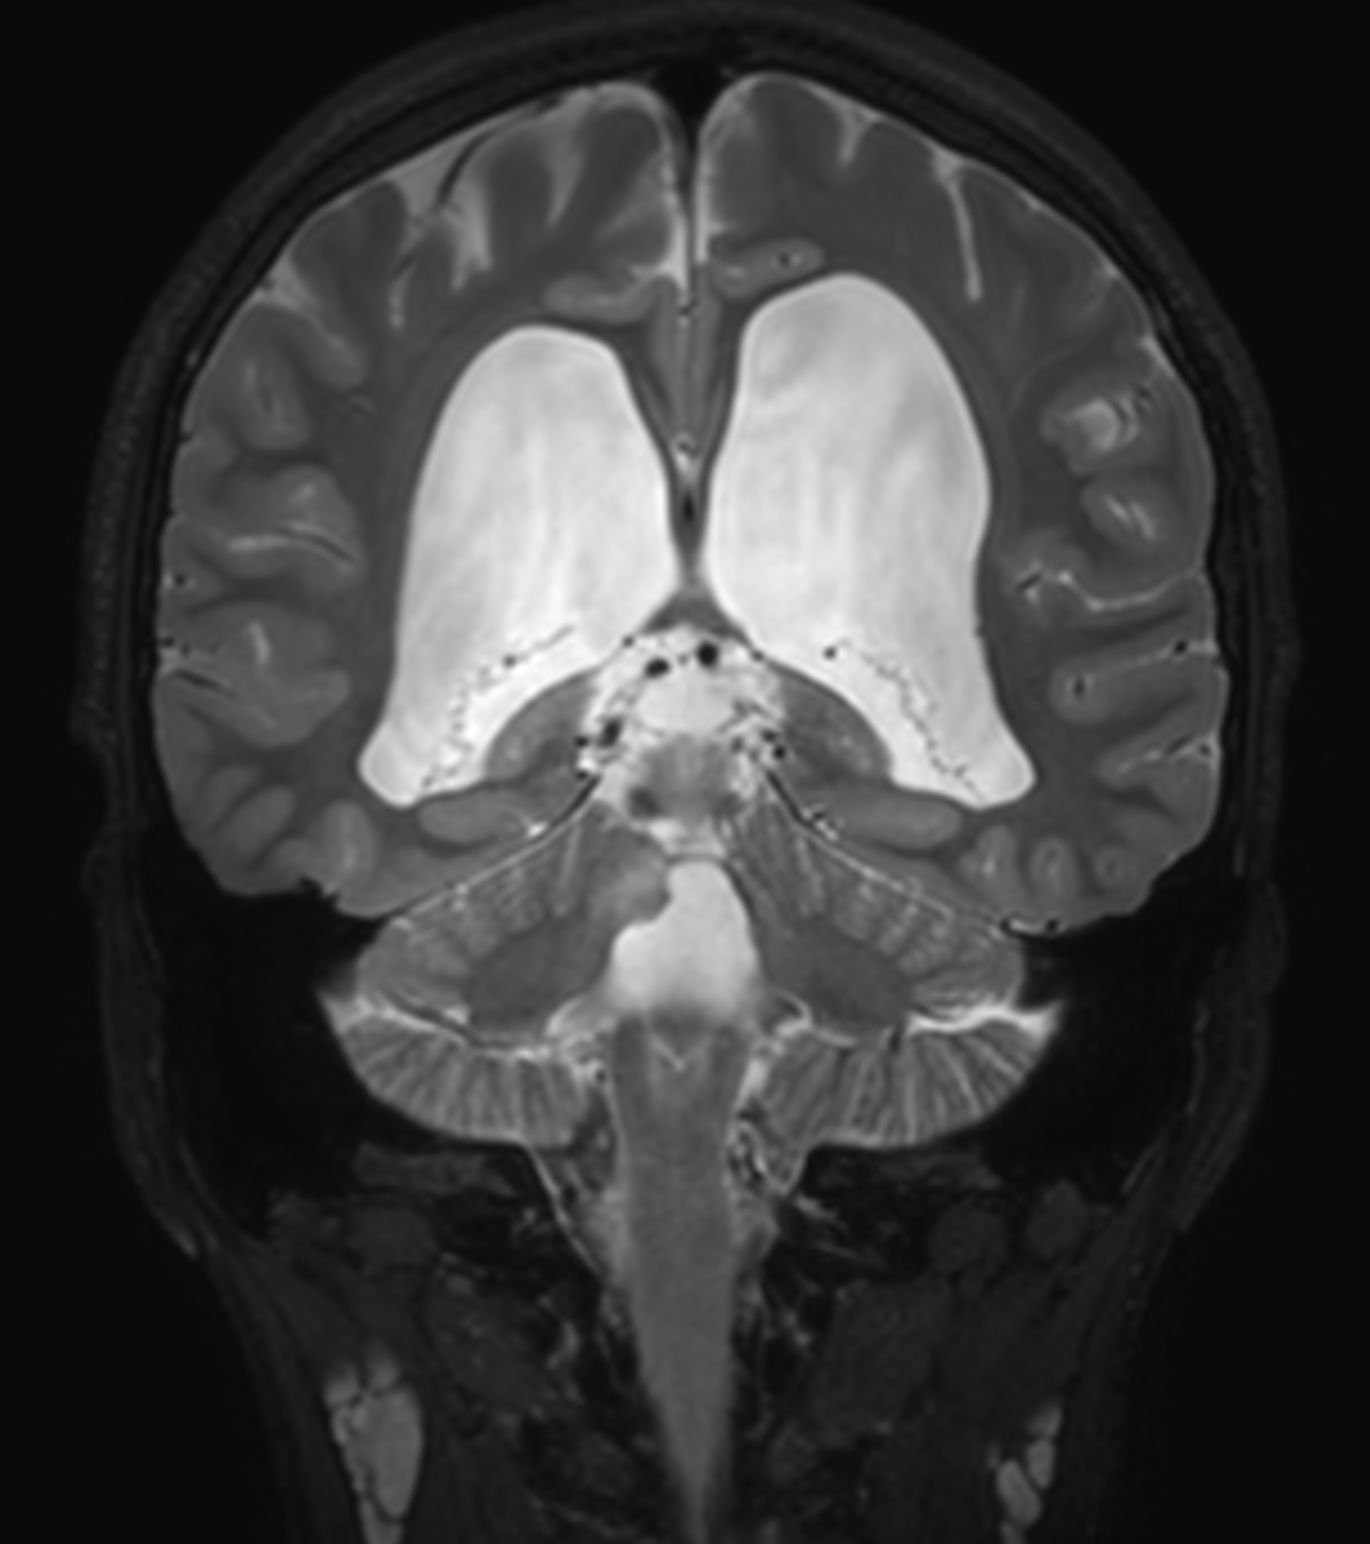

Coronal 3D T2w TSE (reformat)